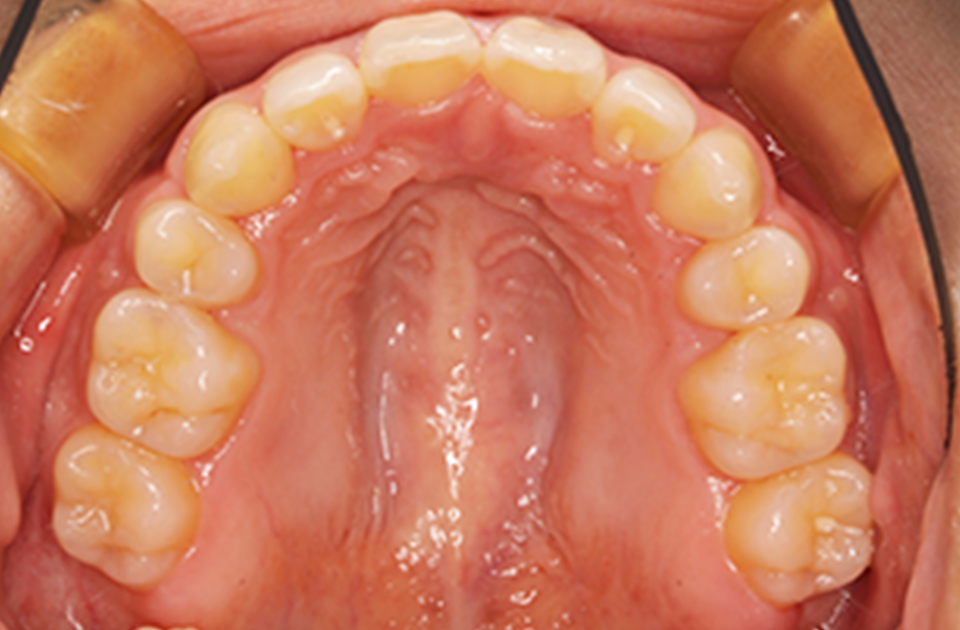

矯正前 上顎

矯正後 上顎